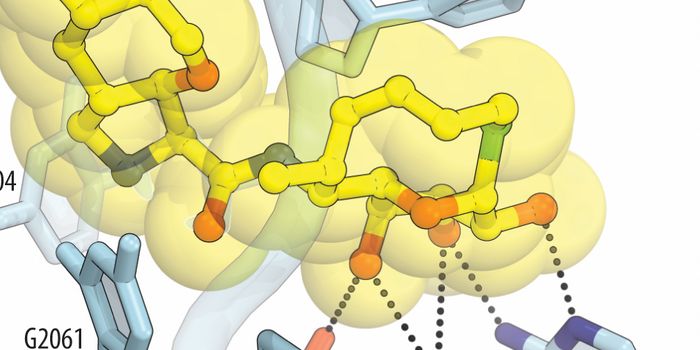

SEP 09, 2024Drug Discovery & DevelopmentThere’s No Turning Back Not long ago, solving the crystal structure of a protein required an entire PhD. Gro ...